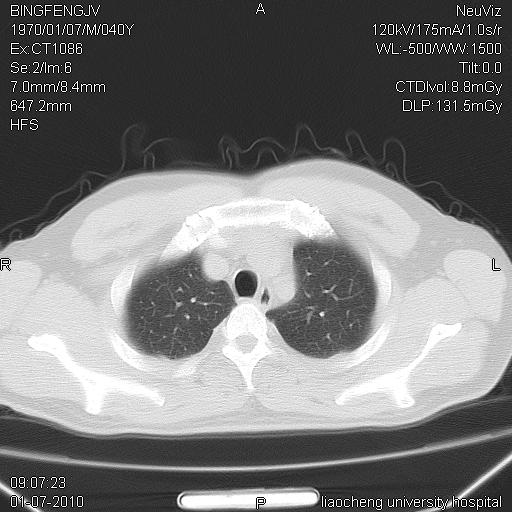

炎症性病灶,继发性改变。

考虑左肺上叶近胸膜下炎症并肺气囊形成。

炎症,大部吸收。